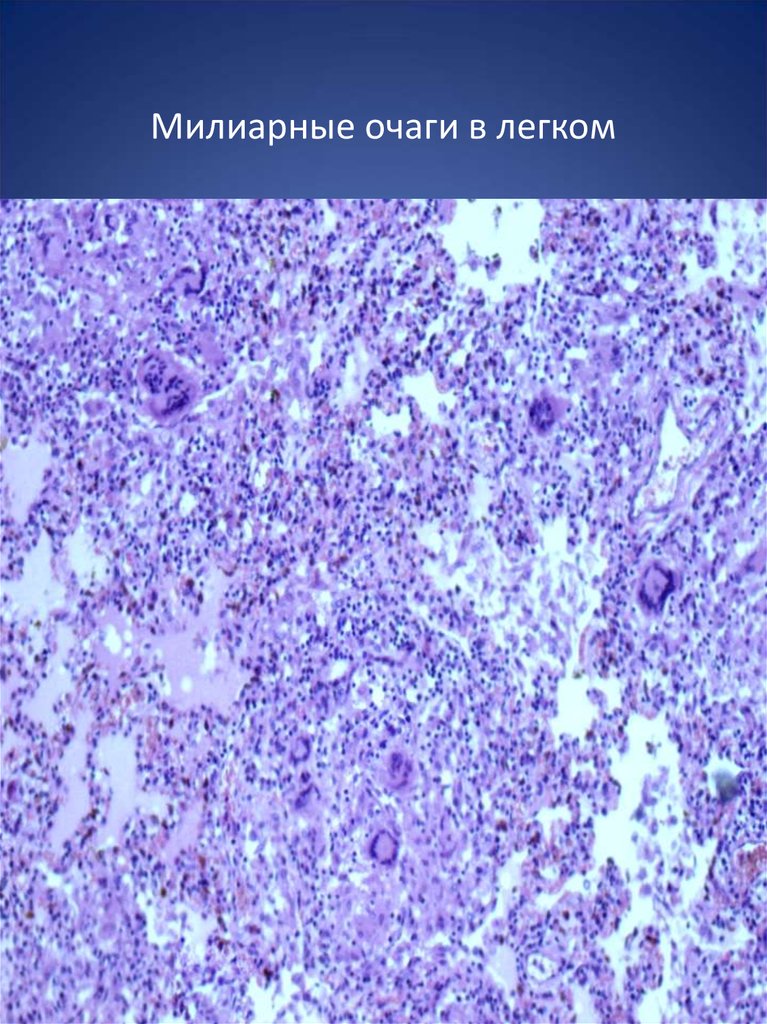

Микроскопический взгляд на мишитарный туберкулез легкого: фотодокументация

Раздел: Снимки-откровения